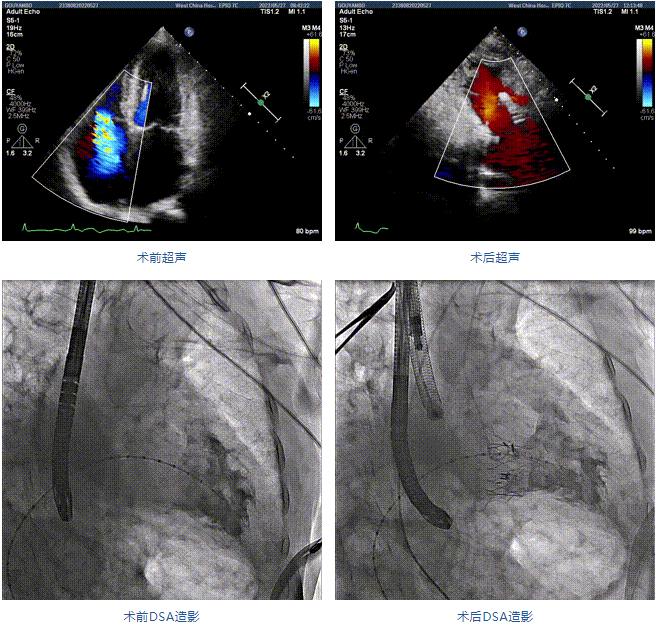

89歲男性。術(shù)前超聲報告顯示:雙房增大,左室壁肥厚,主、肺動脈增寬,三尖瓣重度反流。

團(tuán)隊前期經(jīng)過多次討論,制定了周密的手術(shù)策略和預(yù)案。由于患者已是近九旬的超高齡老人,傳統(tǒng)外科開胸手術(shù)風(fēng)險極高,純介入經(jīng)血管三尖瓣替換能夠明顯減少創(chuàng)傷。術(shù)中陳茂及馮沅教授結(jié)合體表定位在造影指示下精準(zhǔn)穿刺右側(cè)頸靜脈并預(yù)置兩把血管縫合器。成功建立經(jīng)皮血管入路后在食道超聲和DSA的引導(dǎo)下順利完成人工瓣膜植入,術(shù)后超聲和造影顯示人工三尖瓣同軸性良好,瓣架固定牢靠,無反流和瓣周漏,平均跨瓣壓差降為1mmHg。術(shù)畢收緊預(yù)置的血管縫合器縫線完成止血,縫合效果滿意,在手術(shù)室即刻拔除氣管插管。